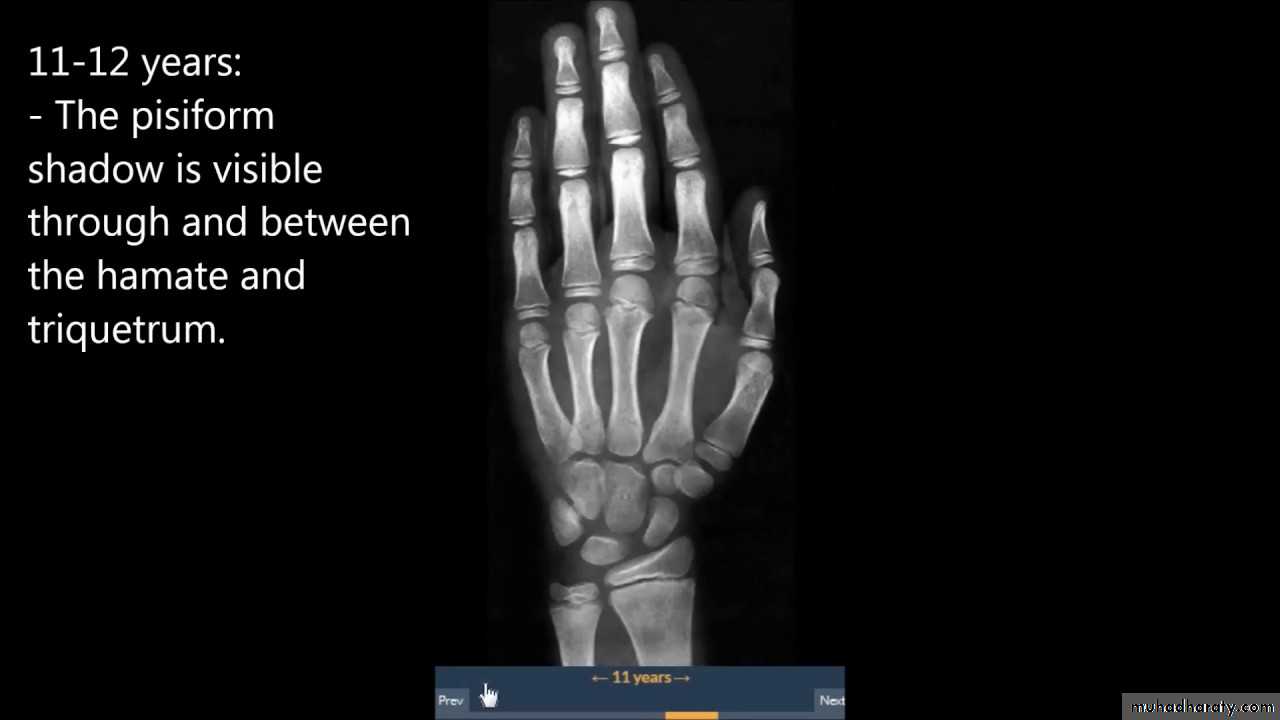

• عمليا يتم تصوير الرسغ والمرفق والكتف لمن يبدوا ظاهرا دون سن العشرين عاما من العمر. ويصور الحرقف لمن بدا في اواسط العقد الثالث من العمر او اقل, والنهاية الانسية للترقوة والتحام القص بالرهابة لمن تجاوز ذلك.

53• معدل ظهور والتحام المراكز التعظمية تبعا للعمر:

• 4) وفي بداية السنة الخامسة يظهر متع للعظم المربع المنحرف وفي نهاية السنة االخامسة يظهر المركز التعظمي لعظمي شبه المنحرف والزورقي الرسغيين.

7) في نهاية السنة التاسعة يظهر متع للنتوء المرفقي لعظم الزند والعظم الحمصي.